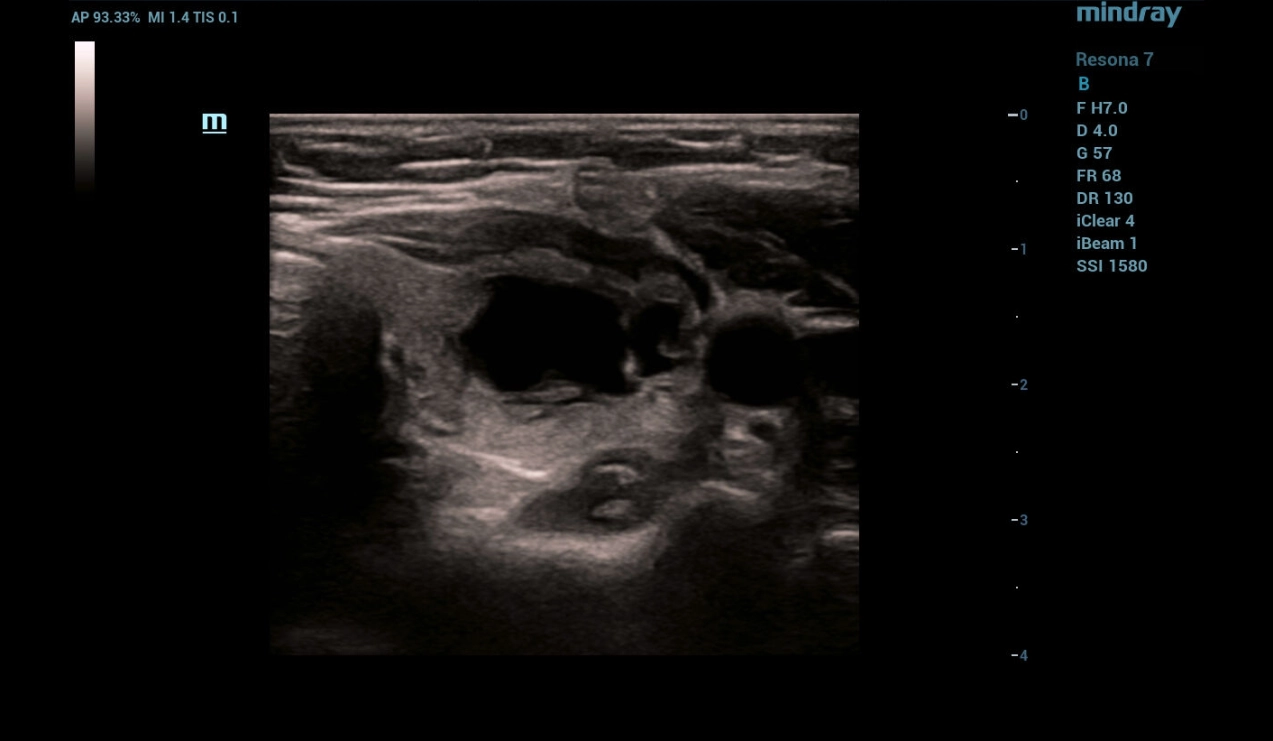

Fine-needle aspiration (FNA) biopsy followed by sclerotherapy with ethanol under ultrasound guidance

Fine-needle aspiration (FNA) biopsy was performed under ultrasound navigation with aspiration of 8.5 ml of clear cystic contents (Fig. 4,5,6) followed by injection of 2.5 ml of sclerosant in the form of 95% alcohol with exposure for 4 minutes (Fig. 7). When sclerosant is injected into the cystic mass cavity in B - mode, the appearance of a hyperechogenic component followed by a decrease in visualization of the needle tip is determined.

Figure 6. Complete evacuation of cystic contents under ultrasound navigation

As the necessary exposure was completed, the sclerosant was evacuated followed by completion of the manipulation and control ultrasound. In - mode a heterogeneous focal formation of the thyroid gland with absence of cystic component was detected (Fig. 8). CFD mode determines absence of blood flow in the focal mass with preserved perinodular vessels (Fig. 9). Strain elastography reveals elastographic heterogeneity of the focal mass with predominance of a soft tissue component (Fig. 10).

Figure 8. Control ultrasound of the thyroid after completion of sclerotherapy

Complete evacuation of the cyst contents was performed under ultrasound navigation with the injection of 2.0 ml of sclerosant with the exposure of 4 minutes and its subsequent removal from the cyst cavity. On control examination, complete recession of the cystic neoplasm walls was determined.